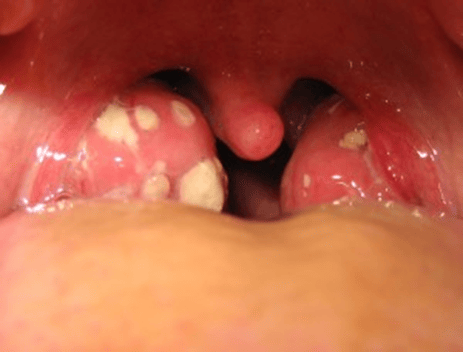

Symptoms are contagious and may include high fever, intense throat pain, large tender lymph nodes in the neck, redness and swelling, difficulty or pain when swallowing, stiff neck, headache, nausea, and white or yellow discoloration on or around the tonsils (see Figure 3). Symptoms usually resolve on their own, and, if they don’t, antibiotics are prescribed if it’s caused by bacteria. If caused by a virus, the symptoms will be treated through anti-inflammatories, pain relievers, hydration, and rest.7

Tonsil stones, also called tonsilloliths or tonsil calculi, are hard bacteria and debris that become stuck in the crypts of the tonsils. It originates as bacteria, debris, mucus, food, and dead cells that bond together in the crevasses of the tonsils. This debris will calcify, forming the stones (see Figure 4).